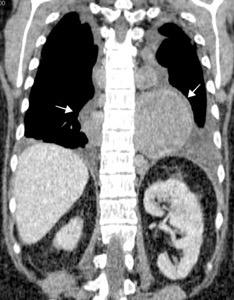

1. < Volumen pulmonar

Fibrosis intersticial

Asbestosis

Sarcoidosis

Fibrosis pulmonar

Neumonitis de hipersensibilidad

Sind. antisintetasa

2.Atelectasia bilateral

3. Enf. neuromuscular

Nason LK. Imaging of the diaphragm: anatomy and function. Radiographics 2012